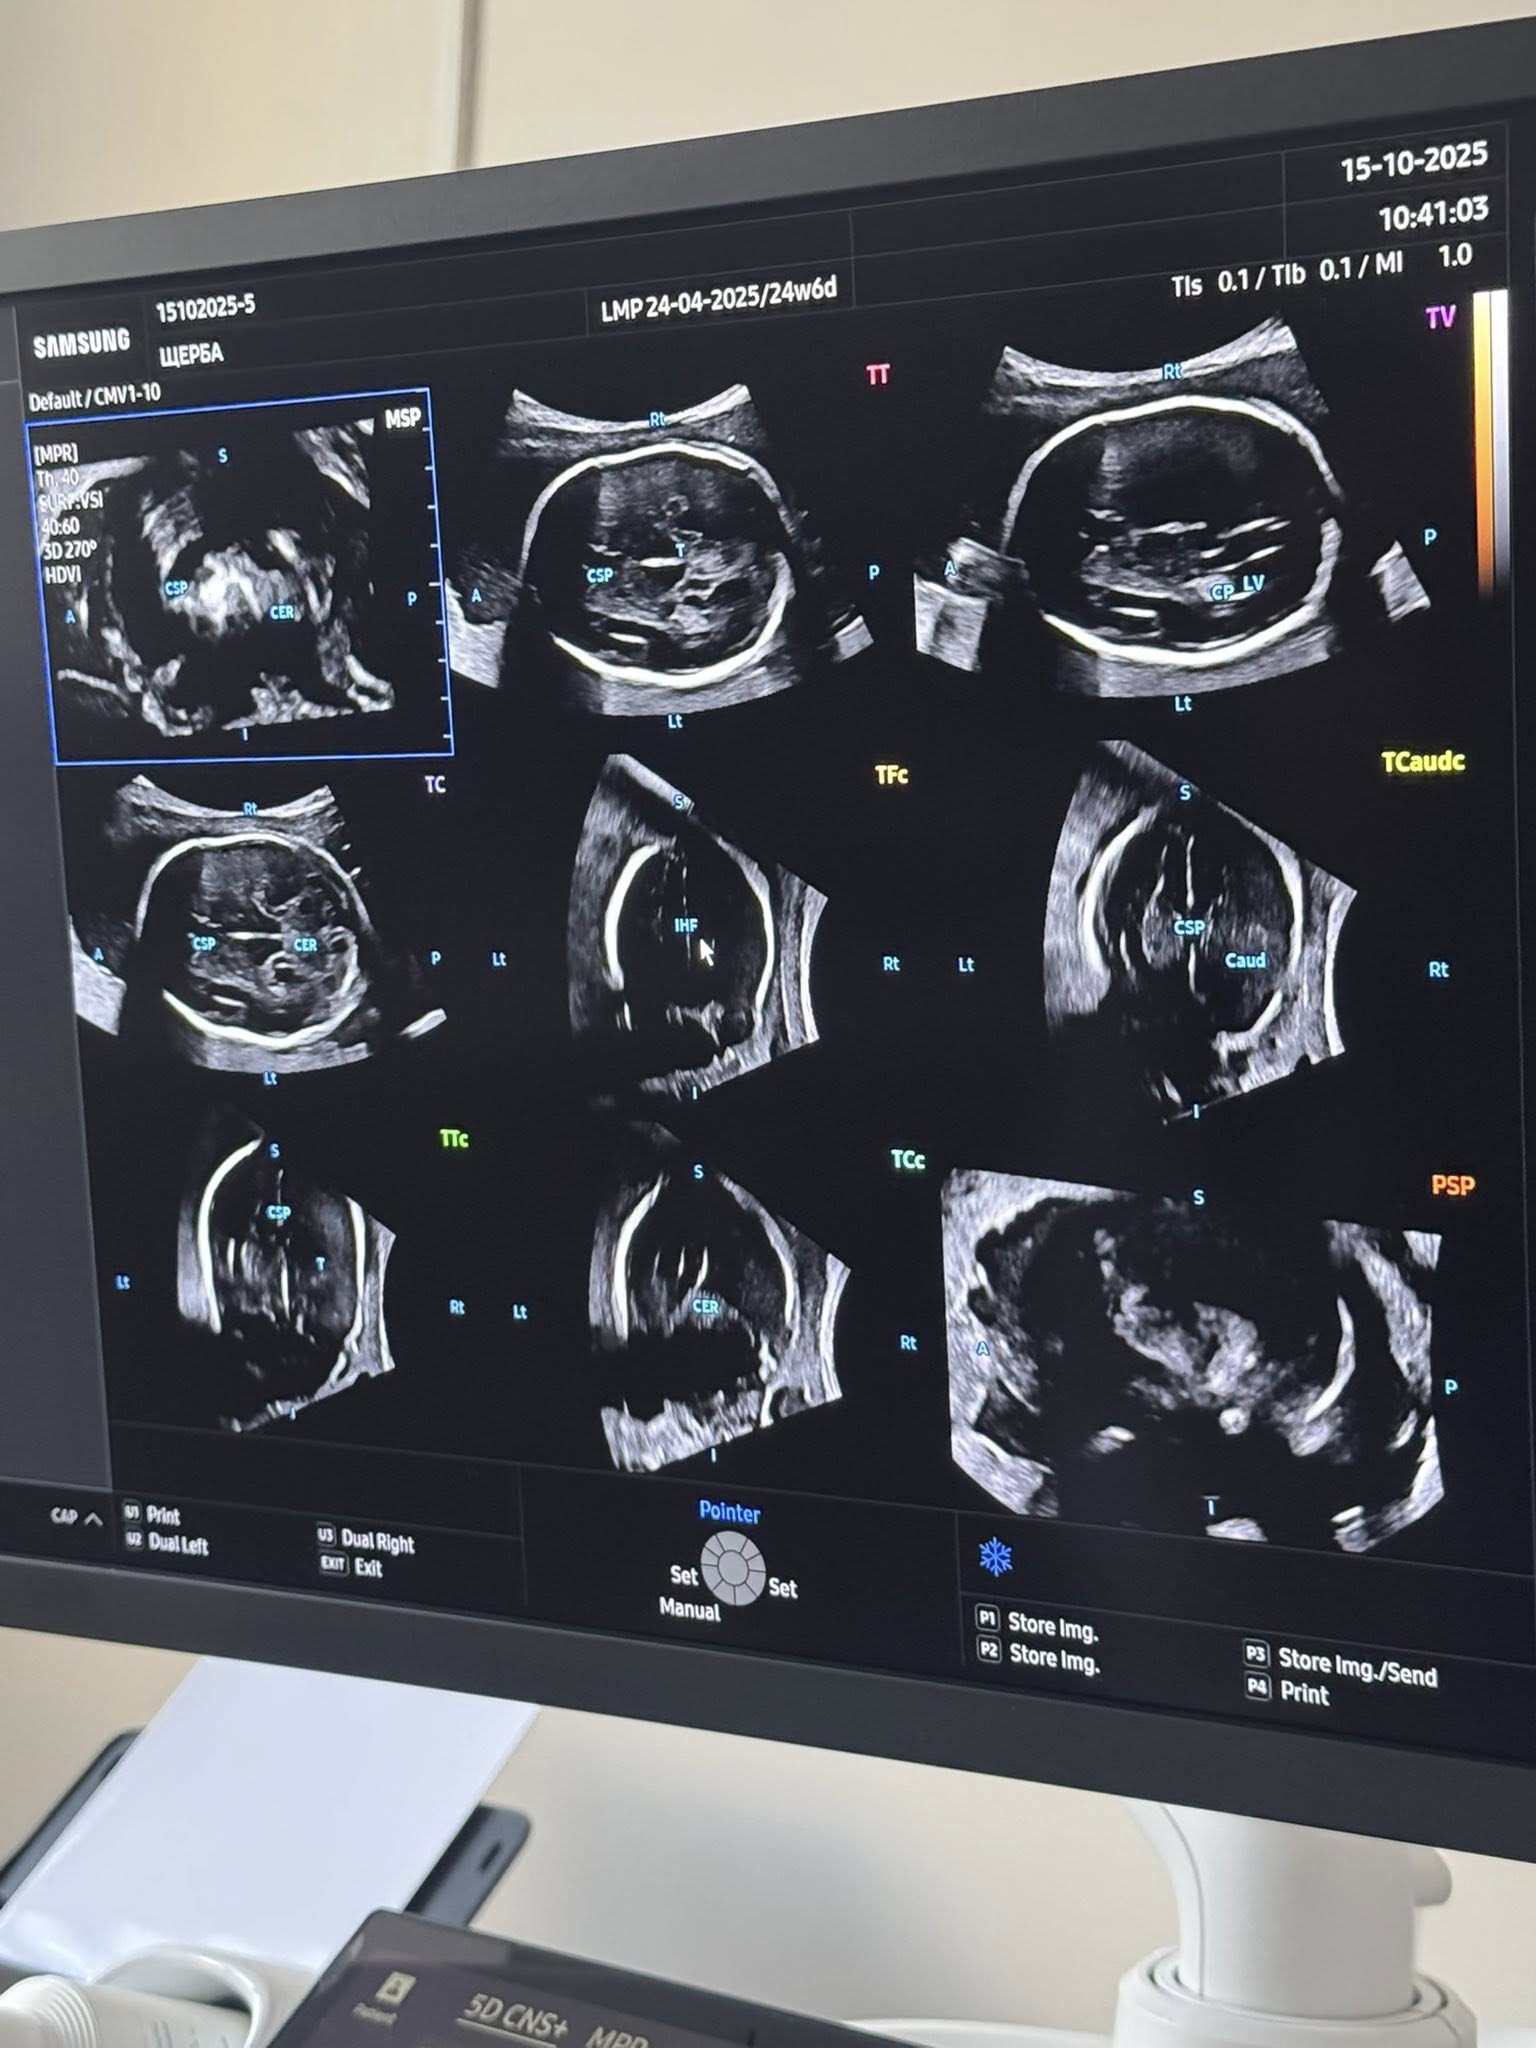

HERA Z20 автоматично розпізнає анатомічні структури, проводить точні вимірювання та формує об’ємні зображення в реальному часі. 5D Ultra Live, Crystal Architecture™ та AI ScanAssist забезпечують неймовірну реалістичність — батьки можуть побачити обличчя й рухи своєї дитини ще до народження.

"Для лікарів це — можливість виявляти найменші відхилення розвитку на ранніх етапах і приймати рішення, що рятують життя. Використання HERA Z20 у Обласний центр планування сім'ї КНП"ВОКЛ ім.М.І.ПироговаВОР" відкриває новий стандарт пренатальної діагностики, спостереження за вагітністю та охорони репродуктивного здоров’я жінок", — кажуть медики.